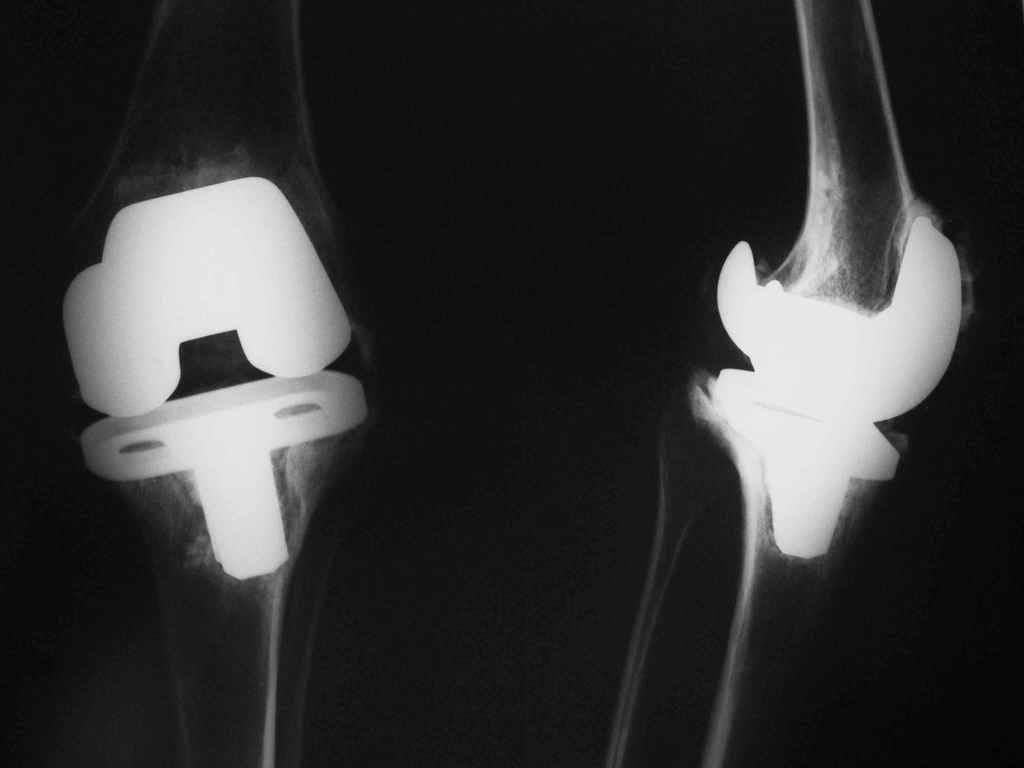

Ревизионное TKR

Кто имеет опыт одно- или двухэтапного ревизионного эндопротезирования коленного сустава при инфицированной нестабильности компонентов эндопротеза?

У пациента с тяжёлой гемофилией через 5 лет после тотального эндопротезирования КС имеются рентгенологические признаки нестабильности компонентов. Около 2-х месяцев назад отметил усиление болей, подъём температуры тела до фебрильных цифр с выбуханием кожи в области послеоперационного рубца с последующим вскрытием и выделением около 10 мл гноя. На фистулографии свищ идёт к большеберцовому компоненту эндопротеза. На фоне антибактериальной терапии свищ самостоятельно закрылся. При посевах отделяемого свища и содержимого, полученного при пункции КС отмечается рост s.aureus. В настоящее время антибактериальная терапия не проводится, отмечается умеренная локальная гипертермия, периодически - субфебрилитет.

Беспокоят боли в КС при ходьбе. Решается вопрос о выборе способа ревизионного эндопротезирования. За двухэтапное эндопротезирование говорит высокий процент эрадикации инфекции (90-95% по данным литературы), против - расшатывание спейсера с формированием большого дефекта проксимального отдела тибии,повторные операции у больного с гемофилией, технические проблемы - отсутствие шаблонов для моделирование спейсеров. За одноэтапное ревизионное TKR - нет необходимости в повторных вмешательствах у больного с гемофилией, против - более низкий процент эррадикации инфекции(70% по литературным данным).С уважением, Мамонов Василий Евгеньевич, ГНЦ РАМН.

Уважаемый Василий Евгеньевич, если есть отправте первичные рентген снимки. Неизбежно двухэтапное вмешательство проводить, слишком рискованно одноэтапная ревизия. А если более гуманно, то артродез коленного сустава...